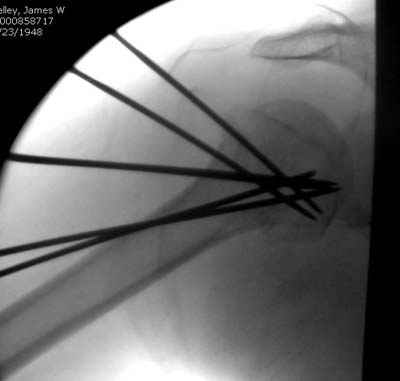

С комментариями абсолютно согласен.

Спицы провожу по передней и задней поверхностям плечевой кости через 4,5 мм отверстия на разных уровнях.

Идеей презентации случая была демонстрация важности постоп Рг - хотя казалось бы все было сделано под флюороскопическим контролем и интраоперационно подозрений на нестабильность не возникло, а такая вот

неожиданность...

Уточни - обе части буквы V вводишь в одно отверстие? А то по снимкам выглядит, что в разные.

V-спица проводится через 4,5 мм отверстие. Видимо, из-за разной длины вторая половина спицы *пролетела* мимо отверстия, что и привело к вторичному смещению костных фрагментов.